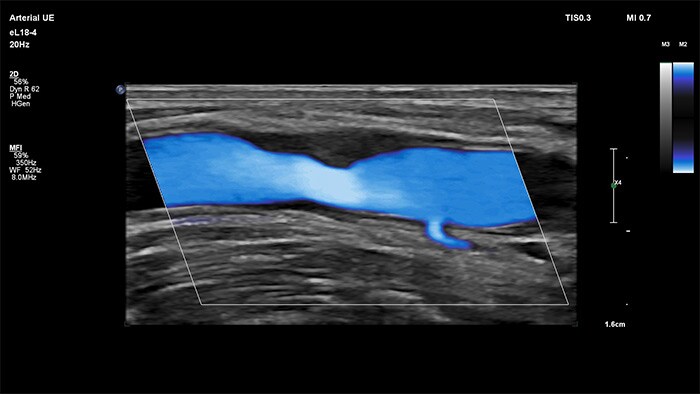

MicroFlow Imaging

MicroFlow Imaging de Philips se ha diseñado para identificar con una extraordinaria sensibilidad las zonas anatómicas que presentan un flujo sanguíneo lento y débil en los tejidos y, además, mejora la resolución del flujo en las exploraciones vasculares. Gracias a su alta resolución y cantidad mínima de artefactos, los profesionales sanitarios pueden visualizar y caracterizar alteraciones sutiles en el flujo alrededor de la placa estenótica para así elaborar diagnósticos fiables.